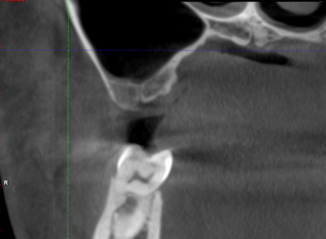

近日我院口腔科接诊了一位后牙缺失患者,要求种植修复。经CBCT检查发现该患者缺牙区上颌窦气化较严重,牙槽骨高度仅为3.6mm,无法进行常规种植修复。

术后CBCT显示上颌窦底充分提升,植体植入位置准确无误。